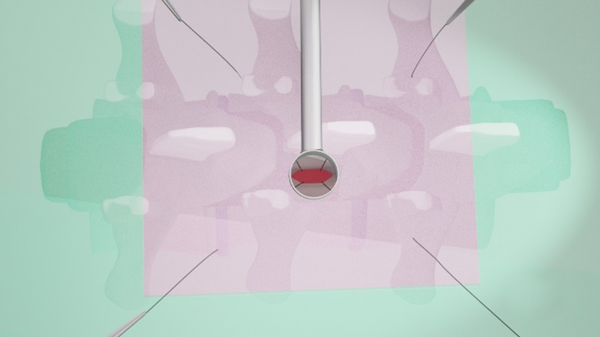

Para describir esta técnica se utilizan las agujas del reloj como referencia posicional, en dónde cefálico es la hora 9 y podálico la hora 3 (fig. 5). Para la retracción dural se requiere de 4 agujas de punción lumbar Nº 19 Gauge enhebradas con suturas de Seda 2.0 (fig. 6). Vamos a tomar como ejemplo un abordaje tubular percutáneo izquierdo en donde el cirujano se posiciona en la hora 6 y el ayudante en la hora 12. Dicho esto, tras la exposición dural luego de una hemilaminectomia, se coloca la primera aguja en hora 5, aproximadamente a 5 cm por fuera del sistema tubular y se punza en dirección del abordaje. Mediante visión microscópica se ve la aparición de la punta de la aguja en el campo quirúrgico, y se toma un extremo de la Seda 2.0 el cual se saca a través del tubo (extremo A), y el otro extremo de la sutura emerge por el sitio de punción tras la extracción de la aguja (extremo B). Ambos extremos se sujetan con una pinza de reparo. Se realiza el mismo procedimiento en hora 7. Del lado medial vamos a tener a las apófisis espinosas como obstáculo, por lo que no hay una constante en el sitio de entrada de las agujas. Puede intentarse introducirlas en horas 11 y 1 desde el lado contralateral, y que pasen por el espacio interespinoso, o bien por horas 10 y 2 desde el mismo lado del abordaje. Con las 4 Sedas 2.0 reparadas, se procede a la apertura dural en forma longitudinal, intentando preservar la aracnoides. Se realiza un punto en el reborde dural de hora 5 con Seda 4.0 y ambos extremos se anudarán con el extremo A de la seda 2.0 correspondiente. Luego de esto se toma el extremo B y se tracciona hasta conseguir que la Seda 4.0 emerja por piel y se fija con la pinza de reparo al campo quirúrgico. Esto último hace que podamos darle mayor o menor tensión a la retracción dural según sea conveniente. Luego se harán los restantes puntos durales de retracción repitiendo la técnica, para así dar comienzo a la etapa de resección tumoral.

Fig. 5: Posición y referencia horaria. Cirujano en posición 6, ayudante en 12 e ingreso de agujas percutáneas en 7, 5, 11 y 1.